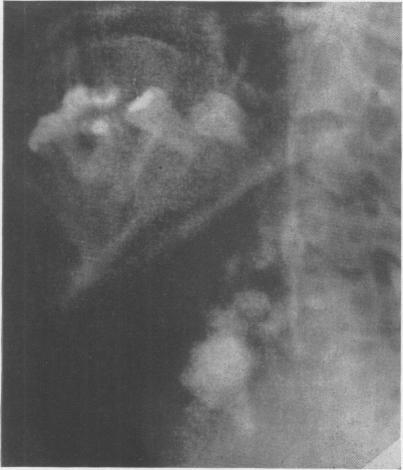

KAPLAN S

Ann Surg. 1951 Apr;133(4):572-3. doi: 10.1097/00000658-195104000-00021.